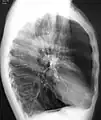

A chest X-ray is not useful to establish a diagnosis of COPD but it is of use in either excluding other conditions or including comorbidities such as pulmonary fibrosis and bronchiectasis. Characteristic signs of COPD on X-ray include hyperinflation (shown by a flattened diaphragm and an increased retrosternal air space) and lung hyperlucency.[5] A saber-sheath trachea may also be shown that is indicative of COPD.[117]

- A lateral chest X-ray of a person with emphysema, displaying barrel chest and flat diaphragm